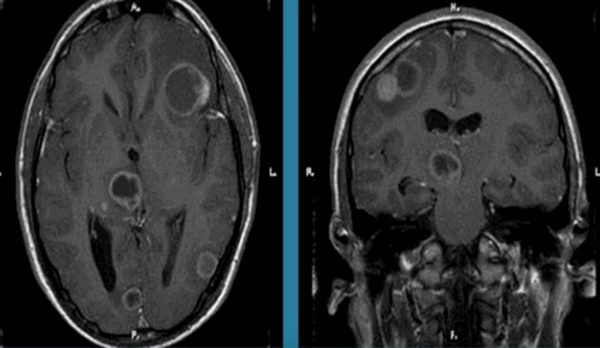

Ишемический инсульт (МР-сканирование)

Очаги ишемии головного мозга на МРТ

Кровоснабжают головной мозг сосуды, образующие в основании черепа в норме замкнутый Виллизиев круг. Далее последние распространяются широкой сетью, делят орган на ограниченные зоны (бассейны). Такое строение обеспечивает поступление кислорода и глюкозы компенсаторно даже при закупорке какого-либо сосуда.

Нарушение кровотока в артериальном бассейне или незамкнутом Виллизиевом круге может сопровождаться формированием обширного участка ишемии. Зона повреждения на МРТ головы будет неправильной формы с нечеткими границами из-за отека. Поражение артерий мелкого калибра выглядит как лакунарный инфаркт (округлая локализованная область изменений).

При продвинутой стадии дисциркуляторной энцефалопатии острое нарушение мозгового кровообращения иногда протекает бессимптомно. Признаки инсульта выявляют только на МР-сканировании. Изменения видны на нативных снимках, контрастирование показано при подозрении на опухоль, вызвавшую ишемию, или энцефалит.